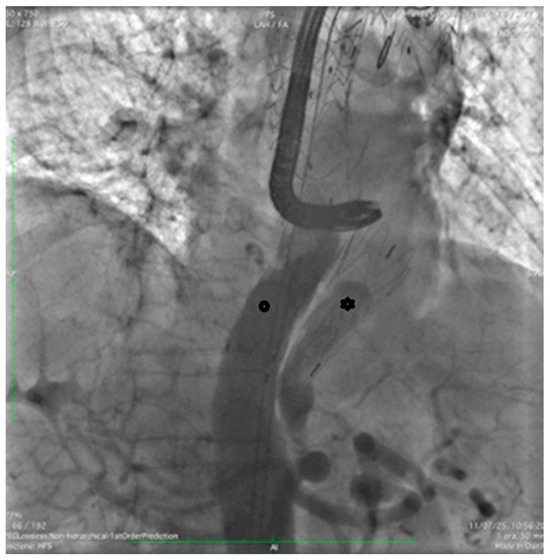

Through the LCFA, a 6F pigtail catheter was advanced into the thoracoabdominal aorta. Intraoperative angiography confirmed substantial FL dilation and two distal re-entry tears beyond the prior TEVAR, with clear retrograde backflow (Figure 2).

Figure 2.

Intraoperative angiography with injection into the true lumen demonstrating marked false lumen dilation with evidence of a distal re-entry tear and retrograde backflow (arrow).